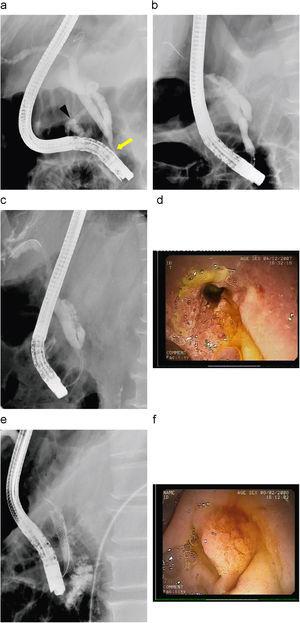

Figura 1. a) Estenosis filiforme de colédoco distal de 20mm de longitud (flecha). b) Prótesis metálica recubierta de 10×40mm recién colocada con vaciamiento completo del contraste de la vía biliar. c) Papila mayor con reacción inflamatoria, y sin visualizar la prótesis metálica. d) Prótesis metálica expandida completamente en el borde de la papila y migrada hacia el interior del colédoco. e) Escara de resección de papila mayor 10 días después. f) Estenosis de colédoco distal dilatada tras retirada de la prótesis (flecha), con un calibre de 4mm.

Se revisó al paciente a los 2 meses y refería dolor abdominal difuso. En la analítica realizada se observó elevación de amilasa con perfil hepático normal. En la duodenoscopia se veía la papila mayor con reacción inflamatoria sin que se consiguieran ver los filamentos de la prótesis (figura 1c), aunque se podía visualizar la prótesis metálica expandida en el borde de la papila mediante la radiología (figura 1d). Se intentó extraer con balón de Fogarty y pinza de cuerpos extraños sin éxito. Ante esta situación, se despegó parcialmente la prótesis mediante needle knife para dejarla visible. El paso siguiente fue la resección parcial con asa de la circunferencia papilar y el intento de movilización de la prótesis mediante pinza de cuerpos extraños. Se continuó con la resección piecemeal peripapilar y se dio argón en el tejido intraprotésico; finalmente, se consiguió sacar la prótesis mediante un asa de polipectomía.

A las 48h apareció hemorragia del borde de la papila mayor, que se controló mediante la inyección de adrenalina 1:10.000 inicialmente y con suero fisiológico; tras el cese de la hemorragia se colocó una prótesis plástica biliar con el fin de evitar complicaciones por el coágulo y la inyección papilar. A la semana se revisó y se pudo apreciar la escara de papilectomía con fibrina (figura 1e) y la expulsión espontánea de la prótesis biliar, junto con la presencia de un buen calibre de la estenosis (figura 1f). Durante su seguimiento en 9 meses, presentó una bioquímica hepática normal sin dilatación de la vía biliar por ecografía y se obtuvo un calibre final de la estenosis superior al conseguido con prótesis plásticas.